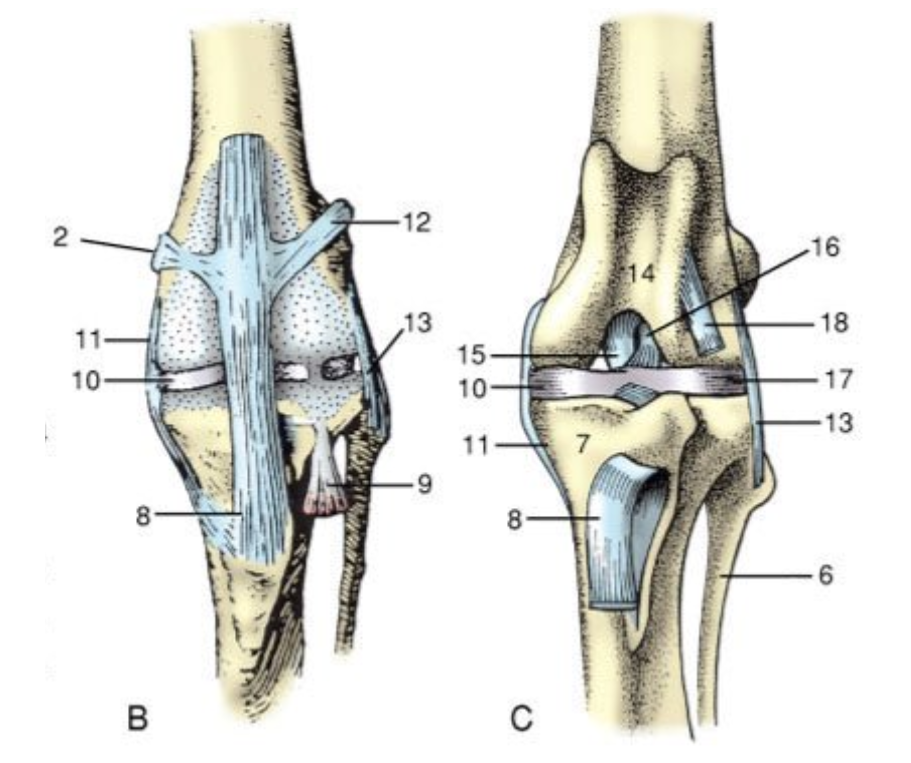

<p>What do these images show?</p>

What do these images show?

proximal tibial articular surface has backward slope

<p>What are 1,2,3 &amp; 4 showing?</p>

What are 1,2,3 & 4 showing?

1. weight-bearing force

2. caudally sloping tibial plateau

3. cranial tibial translation force

4. intact CrCL resists tibial translation